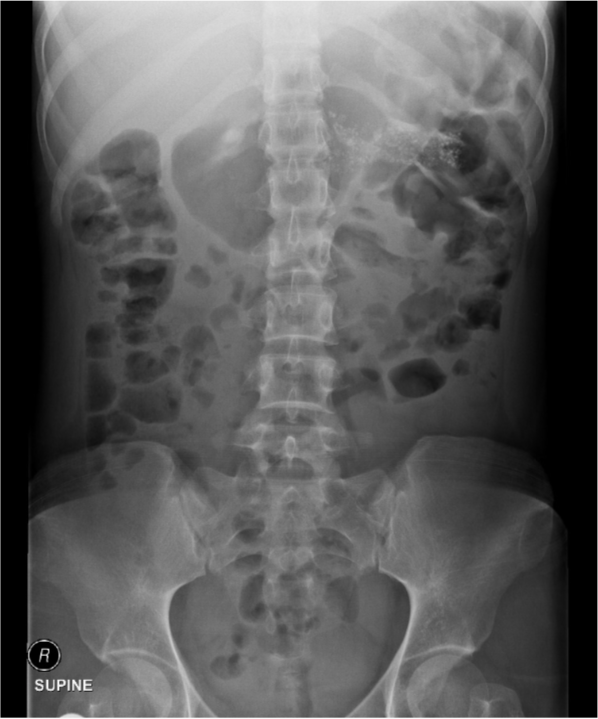

A 49-year old male presented with weight loss despite good appetite. He had loose voluminous stool. The fecal fat content was high. This is a radiograph from the patient: How would you manage this patient?

Pancreatic enzymes